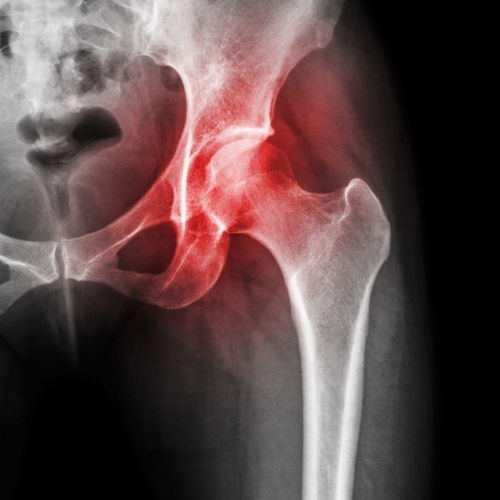

Hip pain can arise from a range of causes including overuse, arthritis, trauma, or tendon and muscle injuries. Because the hip joint supports most of your body’s weight, even minor issues can lead to persistent discomfort and stiffness. At REGENIQUE, we focus on understanding the exact cause of your hip pain—whether it's from the joint, surrounding soft tissues, or referred nerve pain—so your treatment is accurate and effective.

Hip Arthritis

Avn - Avascular Necrosis Hip

Dr. Tushar B Munnoli uses musculoskeletal ultrasound and clinical assessments to identify the source of hip pain—joint, tendon, or nerve.

We use clinical evaluation along with high-resolution ultrasound to pinpoint whether the pain originates in the joint, muscles, or nerves.